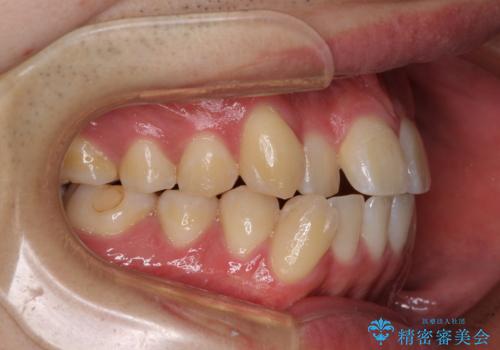

八重歯と前歯のクロスバイト ワイヤー装置で短期間矯正

上顎側切歯(前から2番目の歯)が内側に転位している歯列は、インビザラインでは排列が困難であることが多いため、期間を短く、より良い仕上がりとするため、ワイヤー装置にて矯正治療を行うこととしました。

治療開始の頃は、食事や歯磨きが慣れず、装置が頻繁に脱落しましたが、2,3ヶ月ほどで慣れ、その後は1年ほどで治療を終えることができました。